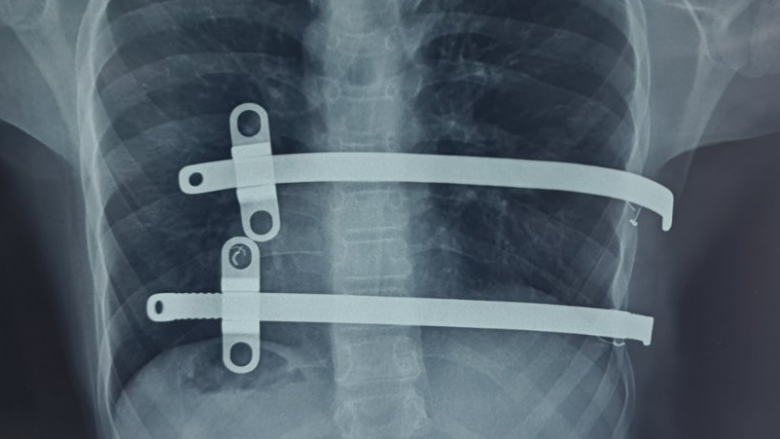

Bëhet fjalë për korrigjim të kafazit të kraharorit me Pectus Bar (pjesë metalike e vendosur në pjesën e përparme të gjoksit).